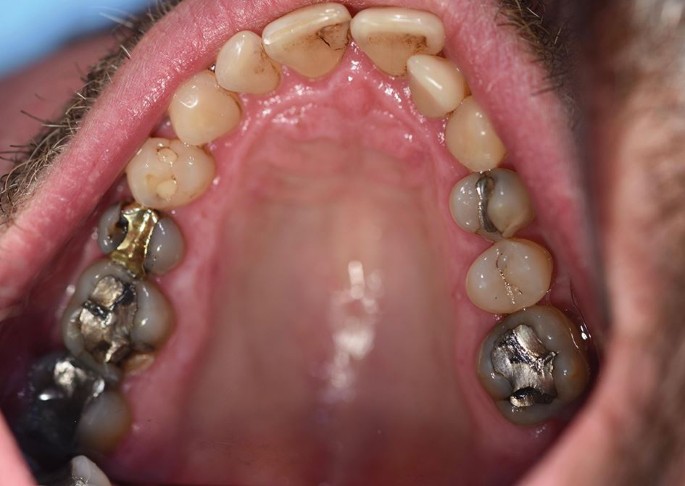

This material can then form the basis for discussions with patients as to the appropriateness of intervention (not the type of intervention). What these assessments cannot establish is a cut-off point beyond which treatment is positively indicated, nor when it is positively contra-indicated, which is in line with the earlier discussion in relation to the difference between cut-off points and the continuum of bruxism. In reality, this matrix looks at 'if' the patient will need intervention, rather than 'when'. Figures 7 and 8 show a 46-year-old patient with RMMA scoring 14 and when compared to Figures 5 and 6 (score 23), shows this variation of need in action.